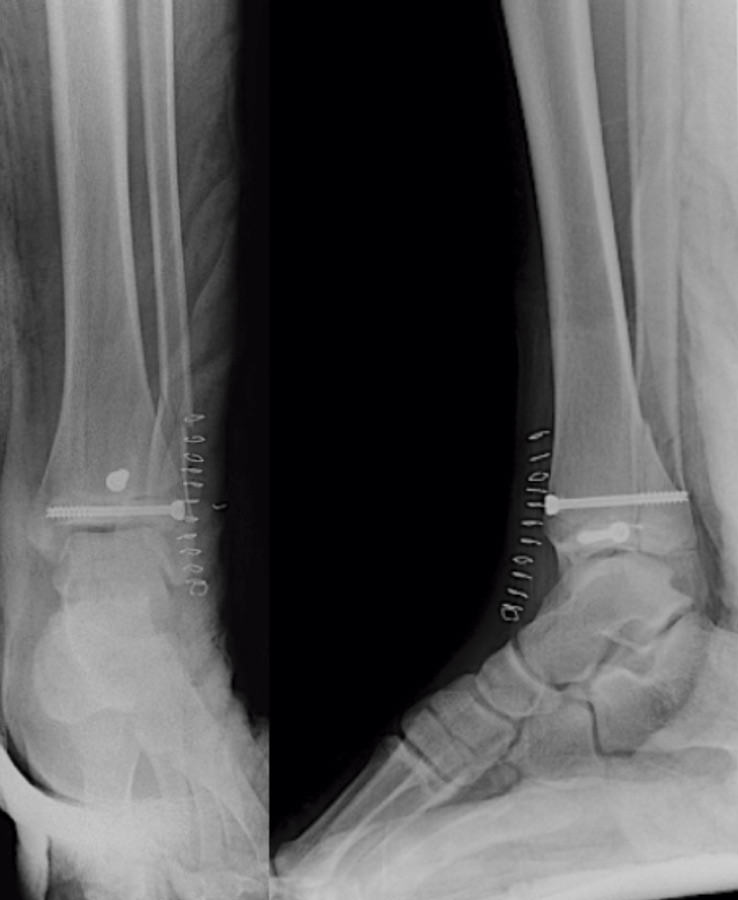

A continuación, realizamos un cierre por planos meticuloso de la cápsula articular, retináculo extensor, subcutáneo y piel, inmovilizando con un yeso suropédico. El paciente presenta una evolución inmediata favorable con dolor controlado, exploración neurovascular normal y control radiológico inmediato correcto (Figura 6).

Figura 6. Control radiológico postoperatorio.